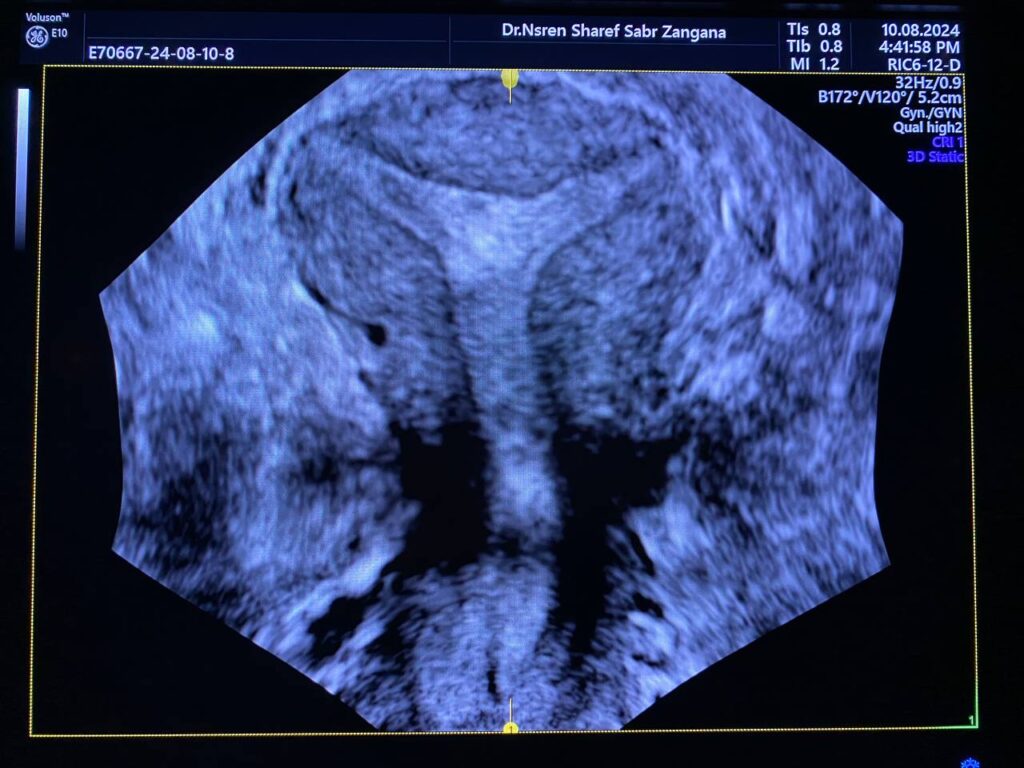

Arcuate fundal surface with fundal depression about 1.5mm, both lateral wall are medially displaced ,narrow cavity, T shape cavity ?? Surface rendering & Omni view